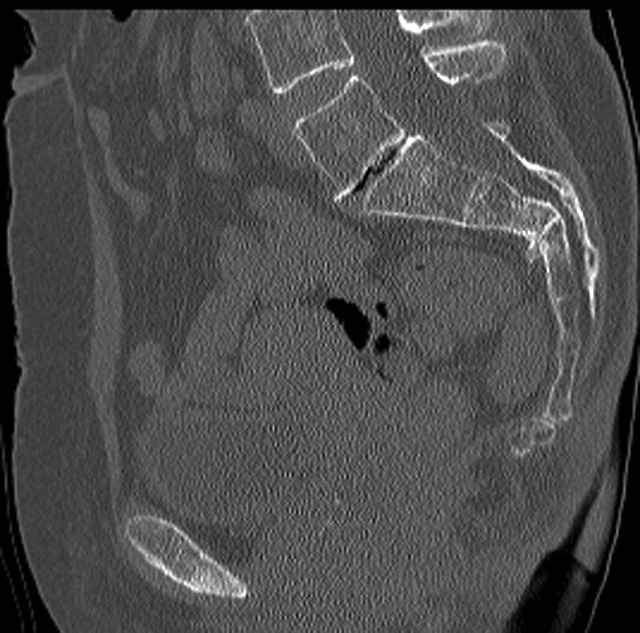

Here are a recent patient’s example slides...

54 yo Female Fell c/o Pain

3 Months After Fall

Continued Pain & Immobility

(+) Instability to Compressive Manual Exam

Pelvic CT Scan - 3 Months After Fall

Sacral Injuries

Ramus Fractures